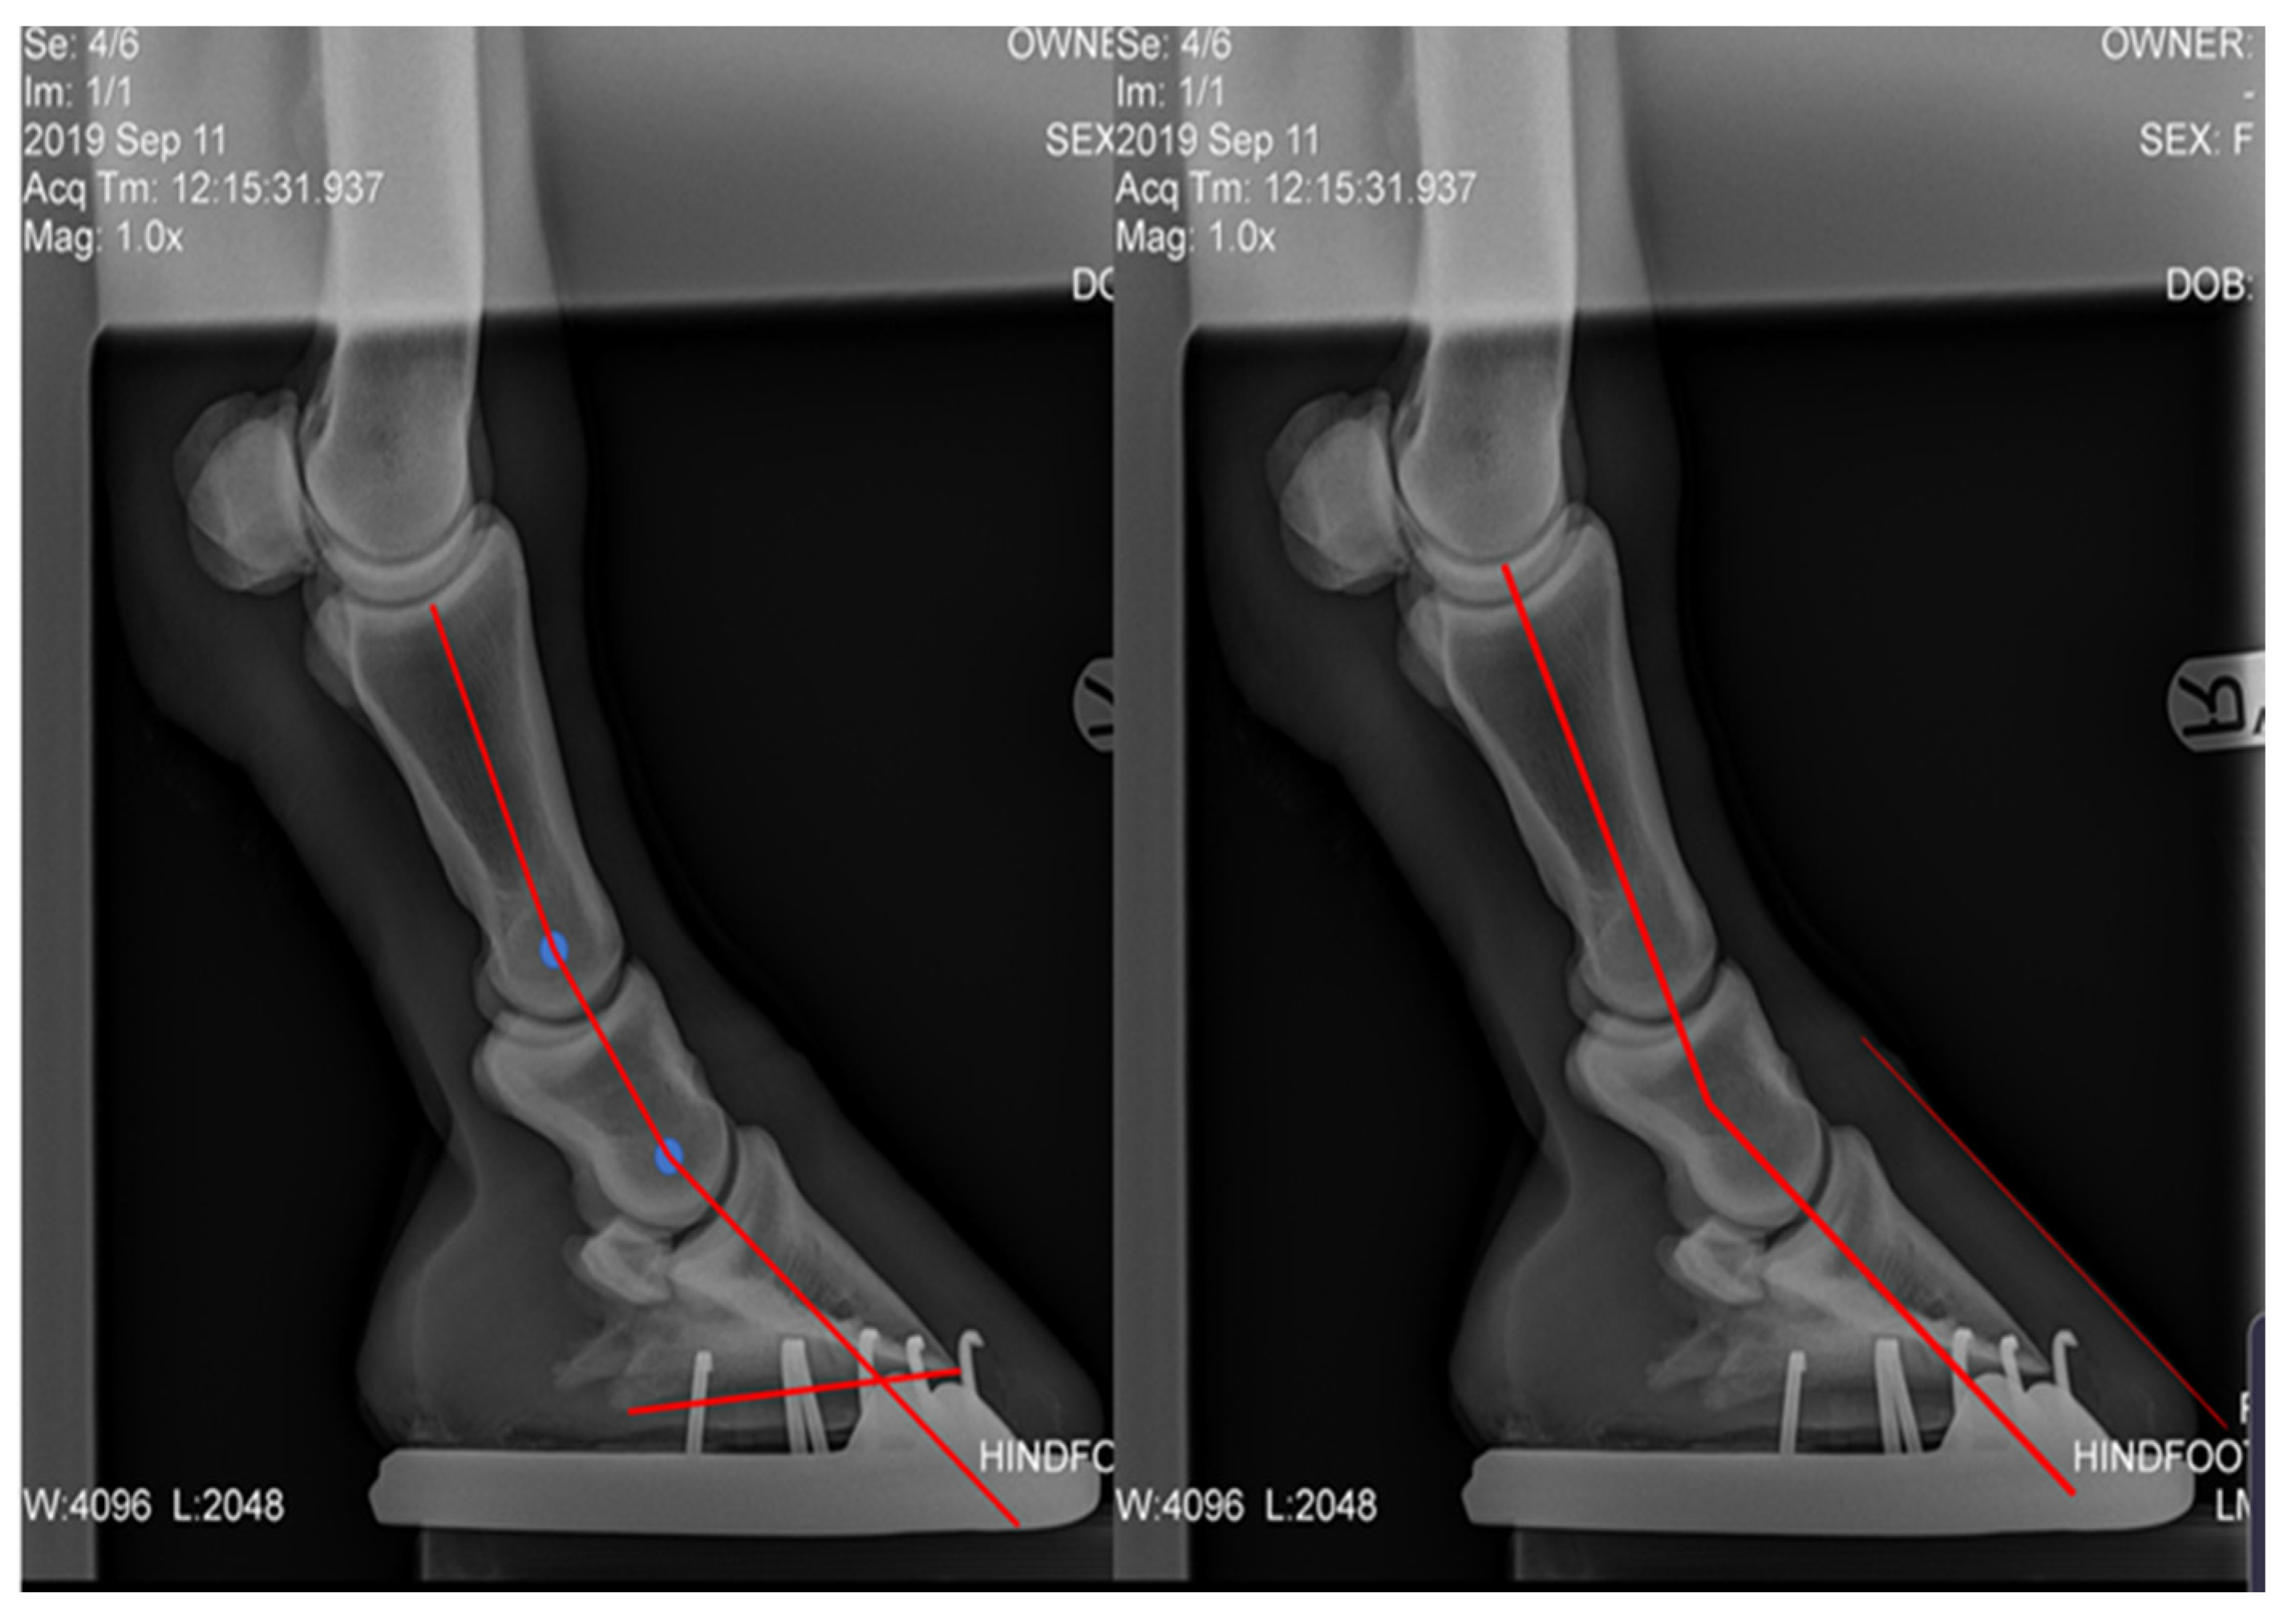

Plantar angle (PA), proximal phalanx to middle phalanx angle difference (P1-P2), middle phalanx to distal phalanx angle difference (P2-P3), and P-DW were measured from lateral radiographs. The radiographs were uploaded into Microsoft PowerPoint, the centre of rotation (COR) of each joint was marked, the axis of each bone was drawn through the COR and the difference in the angle of the axis was collected [28] (Figure 7). The P-DW for the post shoeing group was measured using lateral photographs.

Seven of the initial twelve horses has complete sets of measurements pre and post farriery intervention. Within this group, there was a significant difference in average POBPL pre and post intervention for both the right and left hinds (Table 4). The mean POBPL Mawdsley score when presenting with NPLA was 2.4 ± 0.5 in the right hind and 1.9 ± 0.3 in the left, after intervention these changed to 3.7 ± 0.9 and 3.6 ± 0.7, respectively. There was a significant positive correlation between POBPL and MA for both the right (p = 0.000) and left (p = 0.000). There was a significant difference in CA pre and post intervention for the right but not the left hind. The mean CA pre intervention was 29.7° ± 5.3 for the right and 31.3° ± 3.7 degrees for the left, post intervention averages were 22.7° ± 3.2 and 23.6° ± 3.2, respectively. There was a significant positive correlation between CA and P-DW on both the right (p = 0.001) and left (p = 0.004). There was a significant difference in MA pre and post intervention for both the right and left hind with the average for pre intervention being 81.3° ± 5.1 and post intervention being 88.0° ± 3.8 in the right hind and 74.4° ± 3.7 and 87.1° ± 2.9 in the left hind (Figure 7).

There was a significant difference in HA pre and post intervention in right but not the left hind. There was a significant difference in P-DW for both the right and left hind pre and post intervention (Figure 8).

Figure 7. Two measurement analyses of the same pre-treatment radiograph showing the measurements taken from lateral radiographs. P1-P2, P2-P3, P-DW, and PA. Authors’ own image.

Animals 12 03275 g007